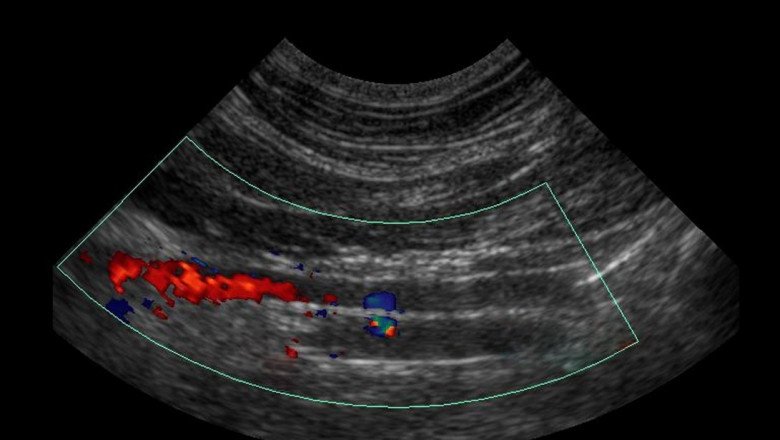

Doppler Ultrasound

Doppler Ultrasound often don't need any prior preparation. If you smoke, you may need to cut back for a few hours before your test since smoking causes your blood vessels to constrict. Your test results might be impacted by this. You won't be subjected to any dangerous radiation during this painless, risk-free process. It's probable that you won't experience much pain. Remove any items, jewelry, and clothes from the study space. You'll be told to lie down on the exam table by the technologist or radiologist, after which a water-soluble gel will be applied to a transducer, a handheld Doppler Ultrasound used for imaging. High-frequency sound waves are sent from the transducer to the arteries or veins under investigation.

To compare the blood pressure in various sections of your limbs, blood pressure cuffs may be placed on several portions of your body (calf, thigh, ankle, and arm). The transducer glides down your arm or leg and rubs against your skin, transmitting sound waves through your tissues and blood vessels before returning to the computer where they are recorded and transformed into a graph or image. The blood moving through your veins and arteries is seen in a picture that appears on a display. You can hear a wooshing sound when blood flow is identified.